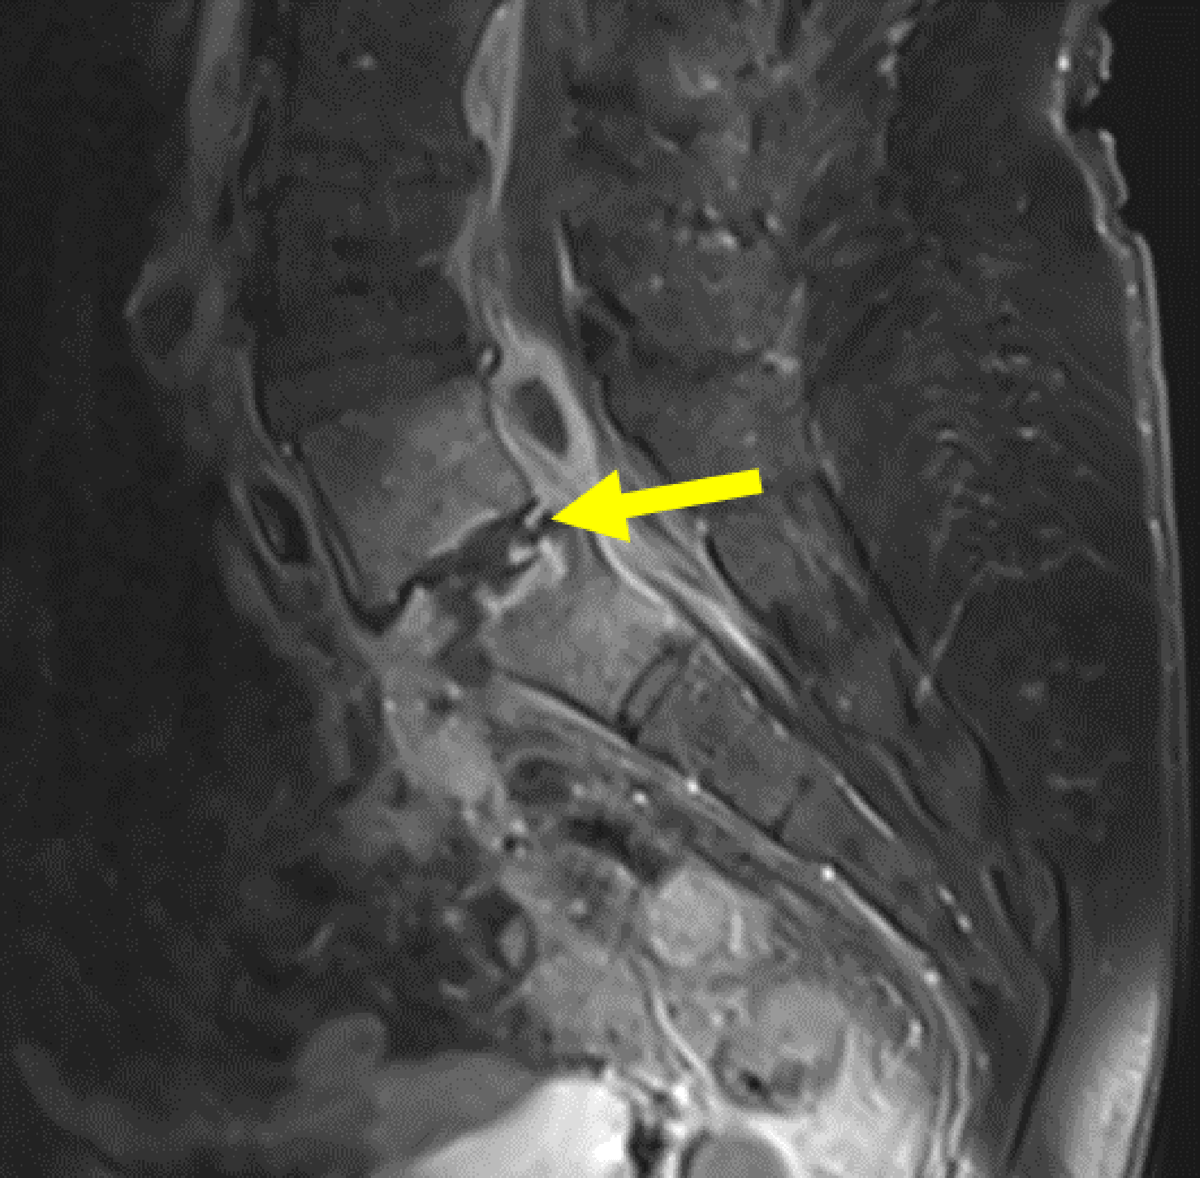

Figure 8

Sagittal contrast MRI in T1 fat saturation weighing: Hyperintense L5-S1 vertebrae and surrounding tissue, showing spondylodiscitis (yellow arrow). There is slight anterolisthesis of L5 upon S1.